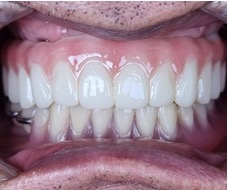

디지털 풀아치 임플란트(상악) & 전체 임플란트(하악) (64세 여성)